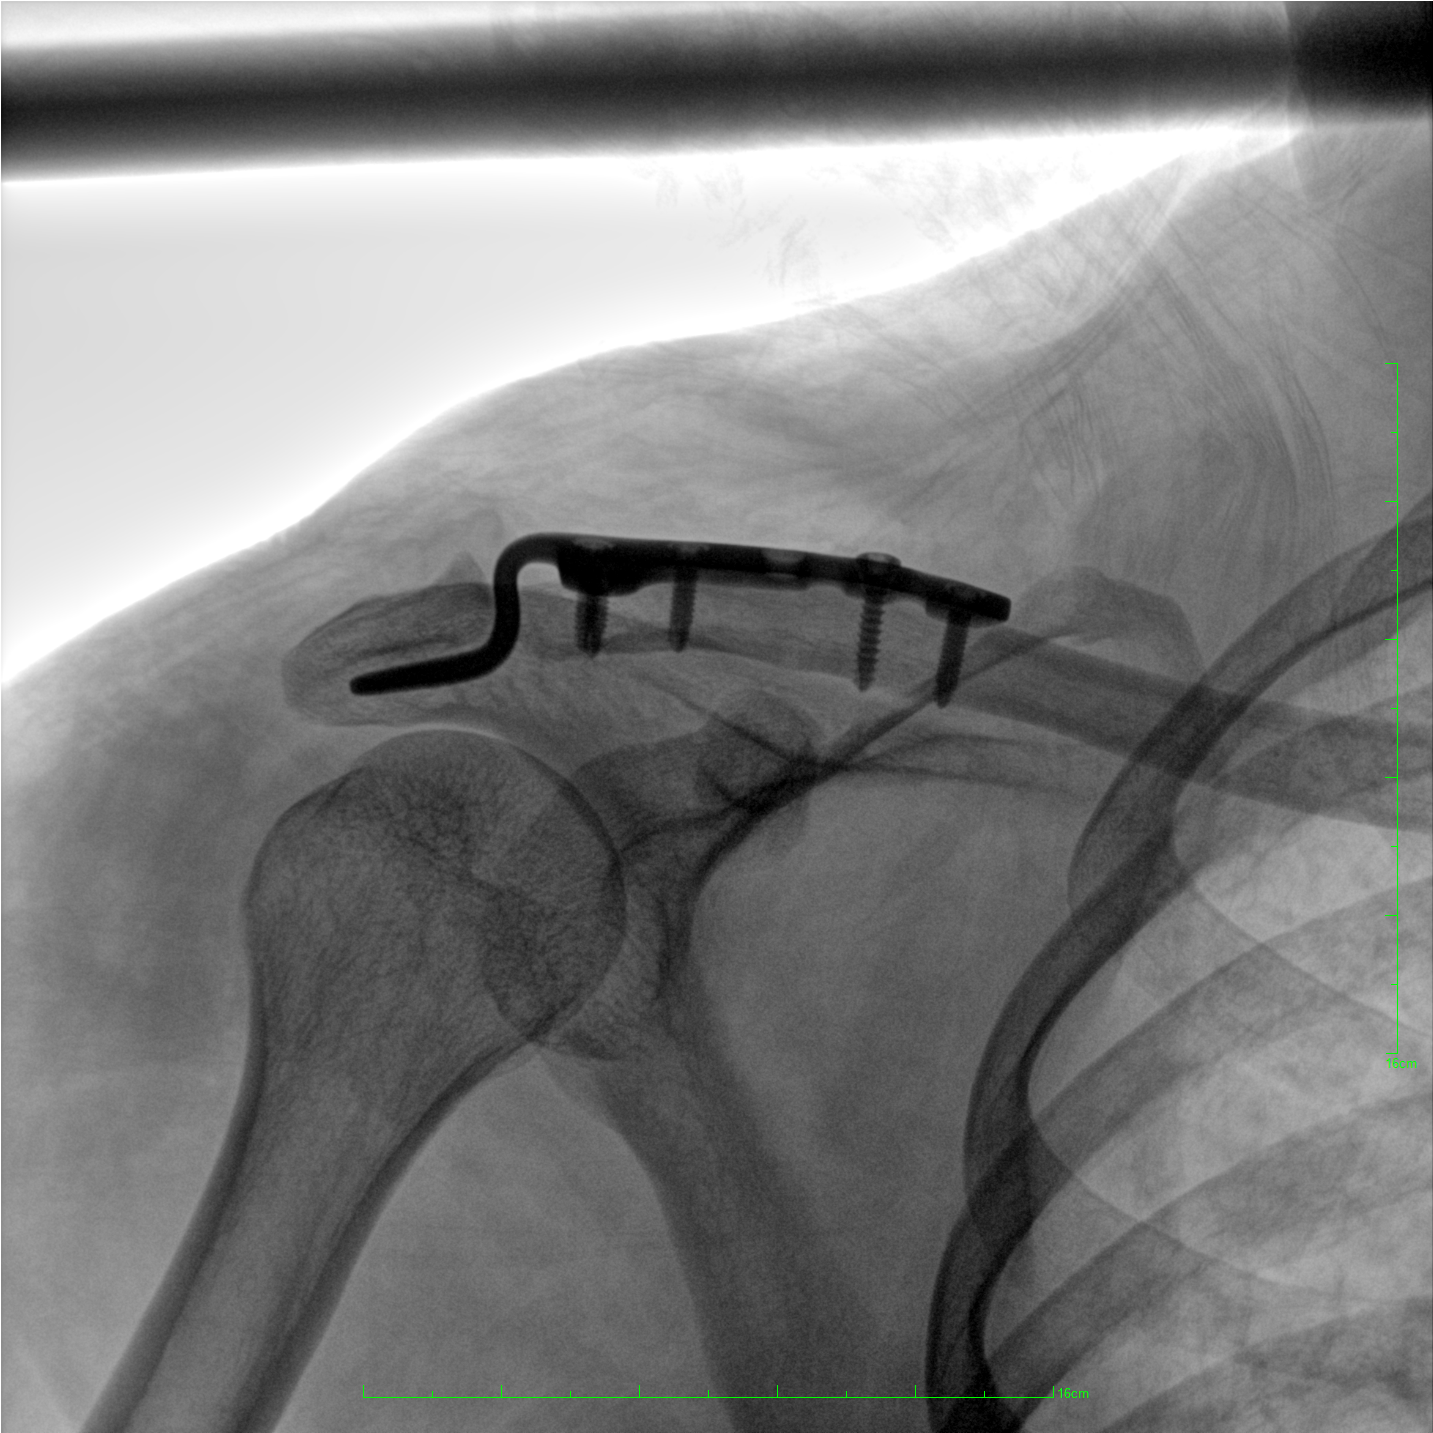

術(shù)中三維成像和橫斷面圖像提供多角度的手術(shù)診斷信息,輔助醫(yī)生進(jìn)行術(shù)中評(píng)估判斷,諸如骨折復(fù)位情況和內(nèi)植入螺釘?shù)某叽绾臀恢茫o助手術(shù)更好地完成。